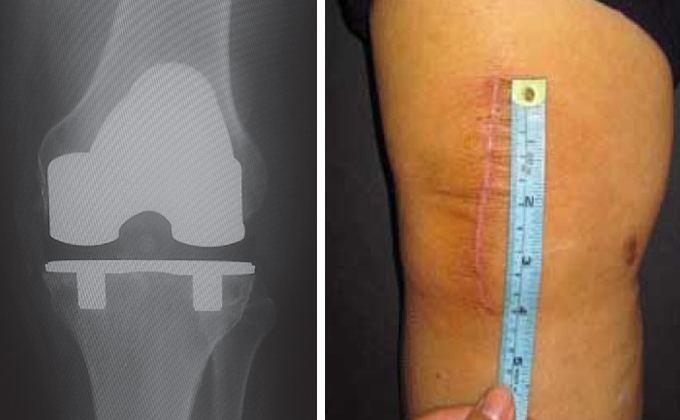

Il concetto moderno di protesi al ginocchio mininvasiva si basa sull’obiettivo di rendere l’intervento meno traumatico possibile e di favorire un recupero rapido del paziente. Oggi non basta più una piccola incisione per definire un intervento come “mininvasivo”: questa definizione riguarda un approccio più ampio, che coinvolge tutta la gestione dell’intervento e della fase post-operatoria.

La protesi mininvasiva del ginocchio è spesso associata, in modo improprio, a tecniche chirurgiche che si distinguono solo per la presenza di una piccola incisione cutanea. In realtà, il significato moderno di chirurgia mininvasiva va oltre l’aspetto estetico: punta a ridurre il trauma sui tessuti durante l’intervento, diminuire il dolore post-operatorio e accelerare i tempi di recupero. L’intervento di protesi al ginocchio, se affrontato con un vero approccio mininvasivo, offre vantaggi concreti per il paziente: questo approccio è considerato oggi una delle innovazioni più importanti nel campo della protesi al ginocchio.

Il concetto di protesi ginocchio mininvasiva è stato introdotto negli anni '90 negli Stati Uniti da J.A. Repicci, inizialmente per la protesi di ginocchio parziale (o monocompartimentale). Nei primi anni 2000, anche le protesi di ginocchio totale mininvasive sono diventate una possibilità concreta, grazie allo sviluppo di quattro tipi di incisioni definite "mininvasive".

Tuttavia, queste tecniche richiedevano l’utilizzo di strumenti avanzati, come la chirurgia robotica e la navigazione computerizzata, necessari per garantire il corretto posizionamento della protesi. L’impiego di tali tecnologie comportava un allungamento dei tempi operatori, un aumento del rischio di infezioni e anche una curva di apprendimento più lunga per il chirurgo. Inoltre, la visione limitata durante l'intervento aumentava il rischio di complicanze, come lesioni a nervi o vasi sanguigni, fratture, danni al tendine rotuleo, rimozione eccessiva dell’osso o posizionamento scorretto dell’impianto. Per questi motivi, l’utilizzo di mini-incisioni è oggi limitato a casi selezionati e principalmente nelle protesi monocompartimentali di ginocchio.